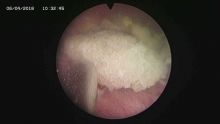

多镜联合治结石 4月6日,处于休假期间,但绥宁县人民医院泌尿外科的医护没有休息,在科主任张华生的带领下,打破常规,挑战高度,成功完成了一台复杂的结石手术。 据悉,患者姓杨,是一位60岁的男性患者,因"间断性左侧腰痛2年,再发伴尿痛2天"入院,经检查后发现患者左肾、左侧输尿管、膀胱内均有多发结石。针对这种结石,传统的手术方法至少需要开3刀,且需分期进行,使得患者痛苦大、治疗周期延长,费用也相应增高。肾结石开刀手术后劳动力会严重散失,即使采用现在流行的微创手术,常规也得分期进行,患者免不了多次手术的痛苦。为进一步减轻患者痛苦,绥宁县人民医院泌尿外科的医师们经过慎重考虑,决定打破常规,制定了多镜联合取石的手术方案。手术在4月6日顺利进行,术中联合膀胱镜、输尿管镜、经皮肾镜进行了长达70分钟的治疗,使得出血量不超过5mL且伤口仅0.5cm,一次性将患者膀胱,左侧输尿管,左肾结石全部取出。术后第五天经复查无任何结石残留,4月13日患者顺利出院。 目前,绥宁县人民医院泌尿外科在微创手术治疗各种尿路结石的技术上,己非常熟练。结石在整个邵阳地区发病率都很高,平常多喝水,每天饮水2000ml以上,调节饮食生活习惯,坚持锻炼可以有效预防结石发生,定期的健康体检也是预防结石的有效措施之一,可以早期发现结石,及时治疗。(图文 付志峰 编辑 谢雅玲) 图为:泌尿外科主任张华生、副主任付志峰进行手术时场景 图为:膀胱结石显象→手术碎石中显像→膀胱结石碎石后显像 图为:输尿管结石显像→输尿管结石碎石后显像 图为:肾结石显像→取出的肾结石标本 图为:术中建立穿刺通道 图为:术后留置的引流管 图为:术后伤口情况 |